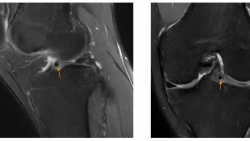

Cảnh giác với triệu chứng đau khớp gối do va chạm

Bệnh nhân 22 tuổi (Hà Nội) đến MEDLATEC Tây Hồ vì đau khớp gối phải dai dẳng. Tháng 7/2024, bệnh nhân gặp tai nạn thể thao, va đập mạnh vào gối phải, gây sưng nhẹ ...